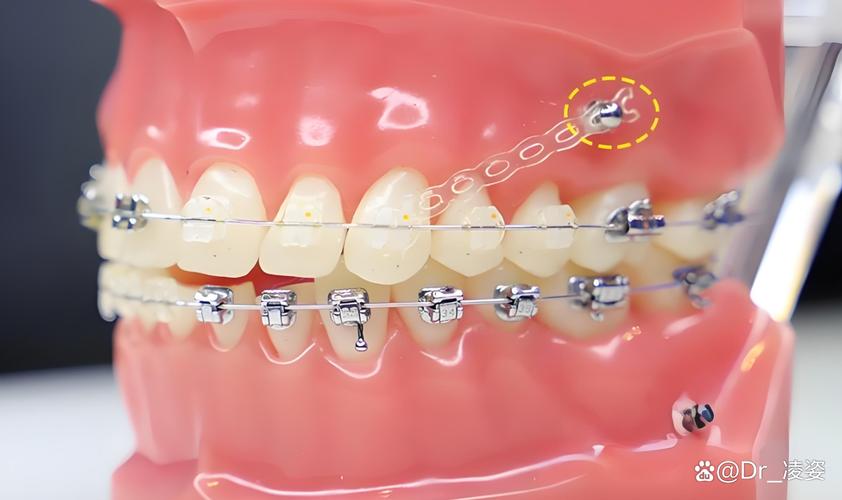

部分患者前牙前突严重,需将门牙大幅向后移动,若仅依赖后牙作支抗,后牙可能向前移位(“支抗丧失”),导致矫正效果打折扣,此时在牙槽骨中植入骨钉,可提供稳定支抗,确保前牙精准内收,同时防止后牙前移。

部分患者因一侧牙齿缺失、龋坏或外伤,导致两侧牙齿移动不对称,中线偏斜,骨钉可辅助向一侧移动牙齿,调整中线至面部正中位置,改善面部美观。